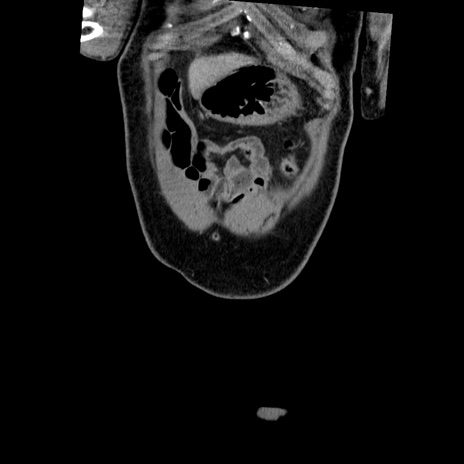

症例22(冠状断像)

【症例】50歳代男性

【主訴】腹痛

【現病歴】AVMからの被殻出血のため回復期リハ病棟入院中。 本日午後3時頃急に下腹部痛が出現した。

【既往歴】AVM、被殻出血、虫垂炎、高血圧

【身体所見】意識晴明、左半身不全麻痺、会話の理解は良好、36.5°C、腹部:膨隆、全体に板状硬、下腹部正中に圧痛点あり、反跳痛-、筋性防御不明、右下腹部にope scar

【データ】WBC 9400、CRP 0.06